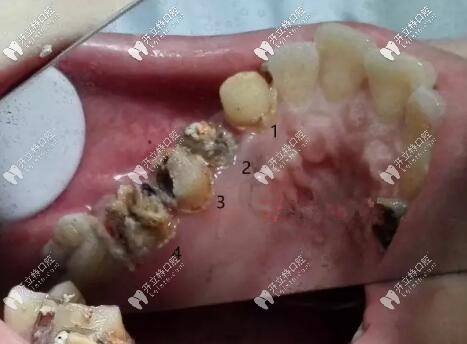

前方高能,看看拆掉口的基牙,我這種情況只能拔掉做種植牙了。

烤瓷冠拆掉后基牙圖片

烤瓷牙尤其那種連著做的連橋冠太多的,兩端基牙承受不住咬合,長(zhǎng)時(shí)間就會(huì)有縫隙,很容易導(dǎo)致基牙齲壞。

烤瓷牙會(huì)刺激牙齦,導(dǎo)致牙齦萎縮,牙冠與基牙不貼合,建議大家要做也做全瓷牙,基牙齲壞幾率會(huì)小一些。